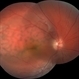

- diffuse choroidal hemangioma

- Fundus camera

- RetCam fluorescein angiogram late venous phase of diffuse choroidal hemangioma